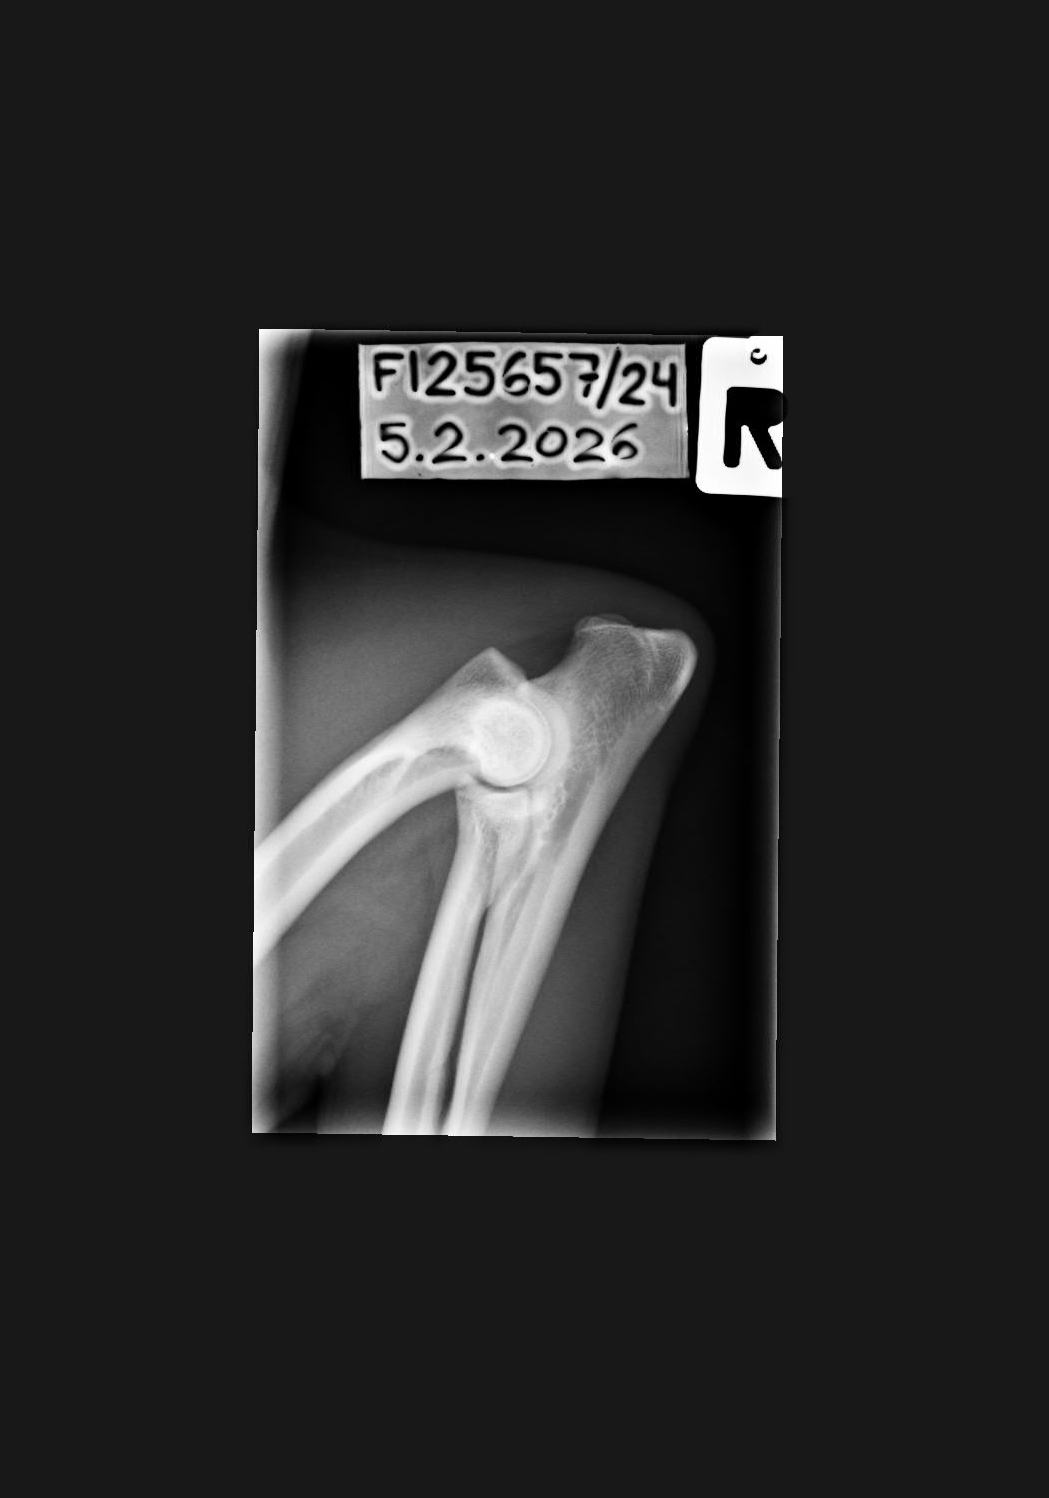

- Finnish Kennel Club's elbow x-ray report Dec '25: Signs suggestive of medial coronoid disease; further information about the condition of the joints can be obtained, if necessary, by computed tomography (CT) examination

- Finnish Kennel Club's elbow CT report Feb '26: A small amount of new bone formation around the medial coronoid process of the left elbow